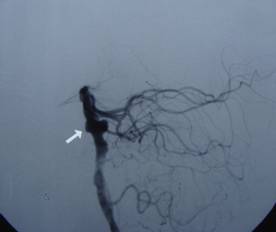

吴某,56岁,因突发昏迷1小时急诊入院。入院时深昏迷,呼吸微弱,血氧和血压降低,双侧瞳孔散大,对光反射迟钝,急诊头颅CT提示蛛网膜下腔出血。入院诊断考虑是脑动脉瘤破裂,紧急行气管插管、止血降颅压等抢救措施,同时放射科陆秀伟主任急诊行全脑血管造影,结果提示基底动脉巨大的动脉瘤(图一)。科主任范学政教授紧急组织全院会诊,组成了包括神经外科、重症医学科、呼吸科、放射科专家抢救小组,采取镇静、脱水、抗血管痉挛以及支持和对症等抢救措施,并病情和影像资料传输到神经外科协助医院四川大学华西医院神经外科远程会诊,会诊认为该病人最佳的治疗方案是行血管内介入治疗。经过充分准备,于入院4日后在华西医院神经外科张昌伟教授联合瑞康医院神经外科医生为患者进行了支架辅助下基底动脉瘤弹簧圈栓塞术,术后行脑血管造影显示动脉瘤完全栓塞(图二)。术后继续予抗血管痉挛等治疗,术后第二天出现呼吸衰竭,肺部感染,后经转入ICU、呼吸科、予以支持、抗感染治疗等综合治疗,术后10天病人清醒,目前患者已经康复出院。

基底动脉瘤